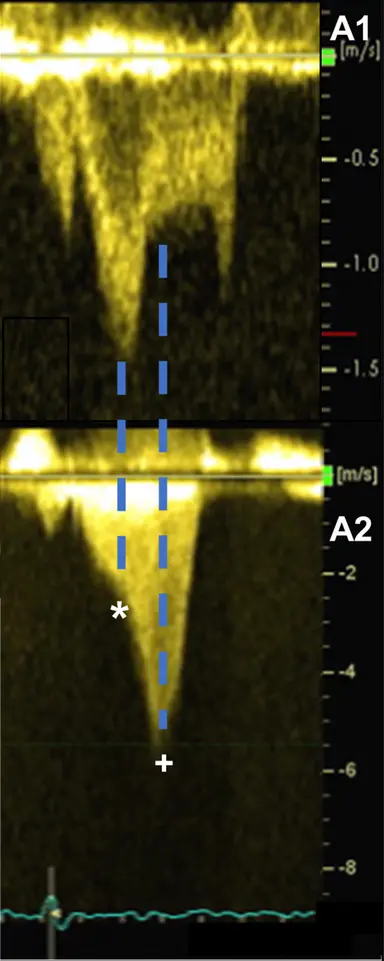

LVOT obstruction is assessed using Continuous Wave Doppler-derived peak instantaneous gradient

⚠️ Make sure you are not getting the MR jet. Easy to happen b/c the MR jet is right next door to the LVOTO.

- MR jet is more rounded

Classically described as having a “dagger”-shaped appearance, but honestly resembles more of a nonworking upper edge of a Bowie knife. 2 Dr. Saghir also used the term “dragon’s tooth,” which I like.

Gradients > 60 mmHg may take on a “lobster claw” pattern 2

- MR jet characteristics can be useful to tease out if 1˚ or 2˚ MR

- MR caused by SAM is typically mid-to-late systolic in timing and posterior or lateral in orientation, owing to the anterior distortion of the mitral valve and compromised leaflet coaptation.1

- Posteriorly-directed MR jet (classically): Usually, the anterior and posterior MV leaflets fail to coapt in mid-late systole, due to the upward and anterior motion of the anterior leaflet toward the LVOT, creating a funnel that directs the MR posteriorly through the interleaflet gap.2

- Contours compared to SAM: